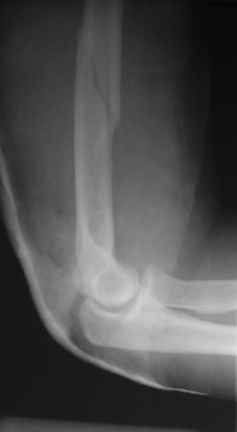

Теперь непосредственно по больному. Лечим функциональной повязкой, добились вот чего (приложение). Будем признательны за дальнейший комментарий - мое мнение, что можно продолжить без операции.

Юрий Алексеевич Булахтин